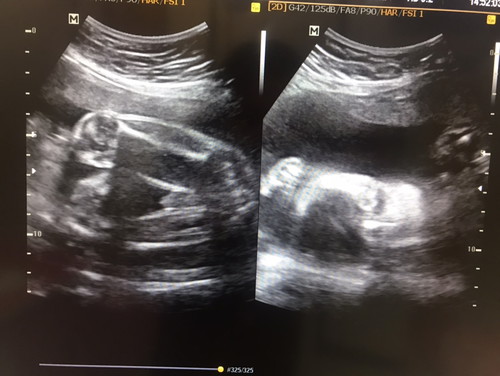

ลูก 25 w น้ำหนักตอนนี้ 1 กิโล แล้วคะ ท้องใหญ่มาก เพศชายจ้า คลอด ตุลา หมอบอกว่าเยอะไป ต้องลดลงบ้างคะ ใครอยากทราบสอบถามได้นะคะ กินให้ลงลูกจ้า